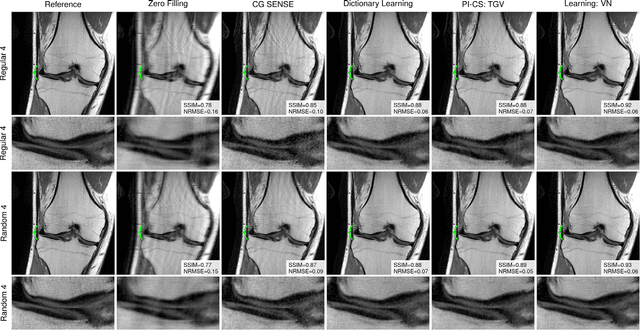

Abstract:Purpose: To allow fast and high-quality reconstruction of clinical accelerated multi-coil MR data by learning a variational network that combines the mathematical structure of variational models with deep learning. Theory and Methods: Generalized compressed sensing reconstruction formulated as a variational model is embedded in an unrolled gradient descent scheme. All parameters of this formulation, including the prior model defined by filter kernels and activation functions as well as the data term weights, are learned during an offline training procedure. The learned model can then be applied online to previously unseen data. Results: The variational network approach is evaluated on a clinical knee imaging protocol. The variational network reconstructions outperform standard reconstruction algorithms in terms of image quality and residual artifacts for all tested acceleration factors and sampling patterns. Conclusion: Variational network reconstructions preserve the natural appearance of MR images as well as pathologies that were not included in the training data set. Due to its high computational performance, i.e., reconstruction time of 193 ms on a single graphics card, and the omission of parameter tuning once the network is trained, this new approach to image reconstruction can easily be integrated into clinical workflow.